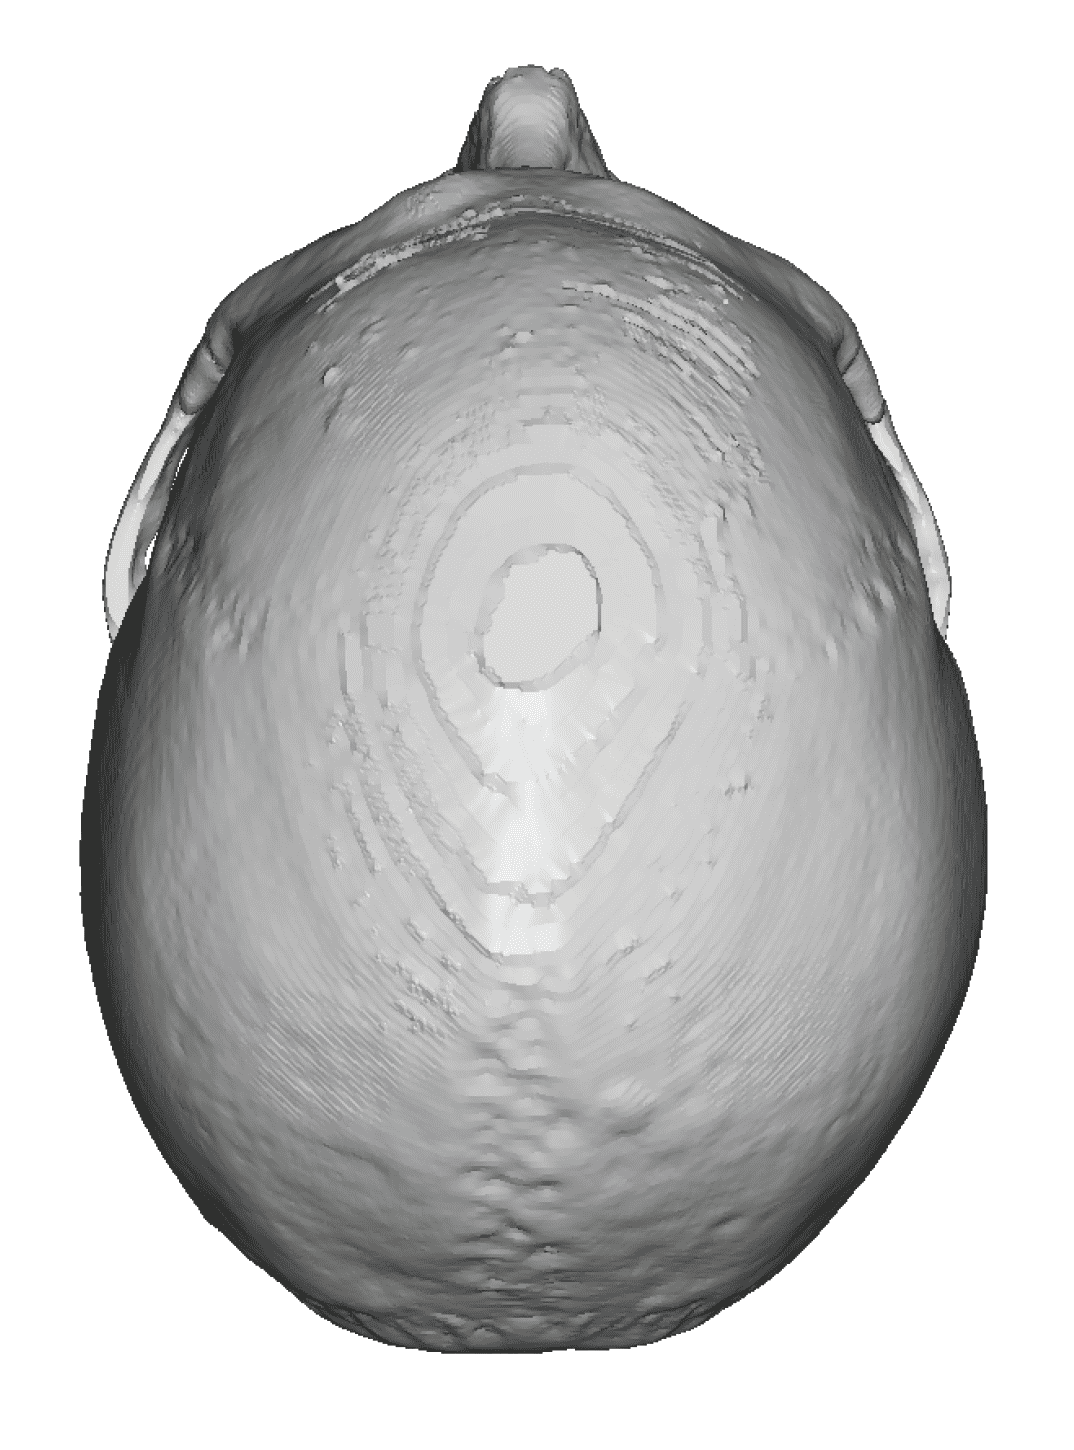

Severe narrowing skull deformity from prior sagittal craniosynostosis repair as an adult.

Complete replacement of entire skull by a custom implant with temporal fat injections.